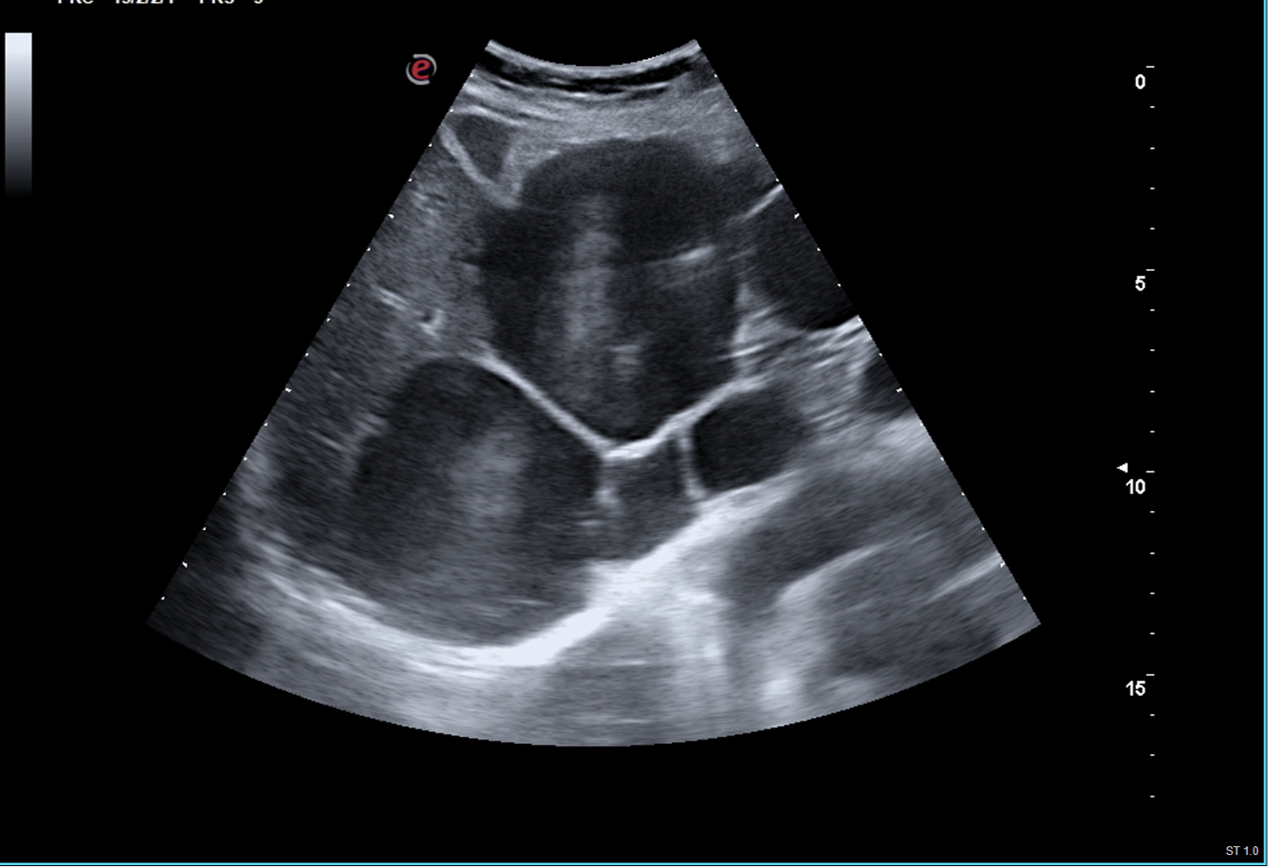

Hallazgos ecográficos

Ecografía: Hígado aumentado de tamaño con presencia de múltiples quistes simples (> 8), algunos de ellos tabicados, el mayor de 62 mm, con presencia de imagen heterogénea calcificada sin vascularización central ni periférica en lóbulo hepático derecho, segmento V-VI de 34 mm. Páncreas parcialmente visualizado sin lesiones. Riñón derecho con presencia de quiste cortical simple de 52 mm, sin otras lesiones, sin ectasia. Riñón izquierdo de tamaño y morfología normal sin lesiones, sin ectasia. Bazo sin alteraciones de tamaño normal. Vejiga adecuadamente replecionada con paredes levemente engrosadas, residuo postmiccional 30 ml.